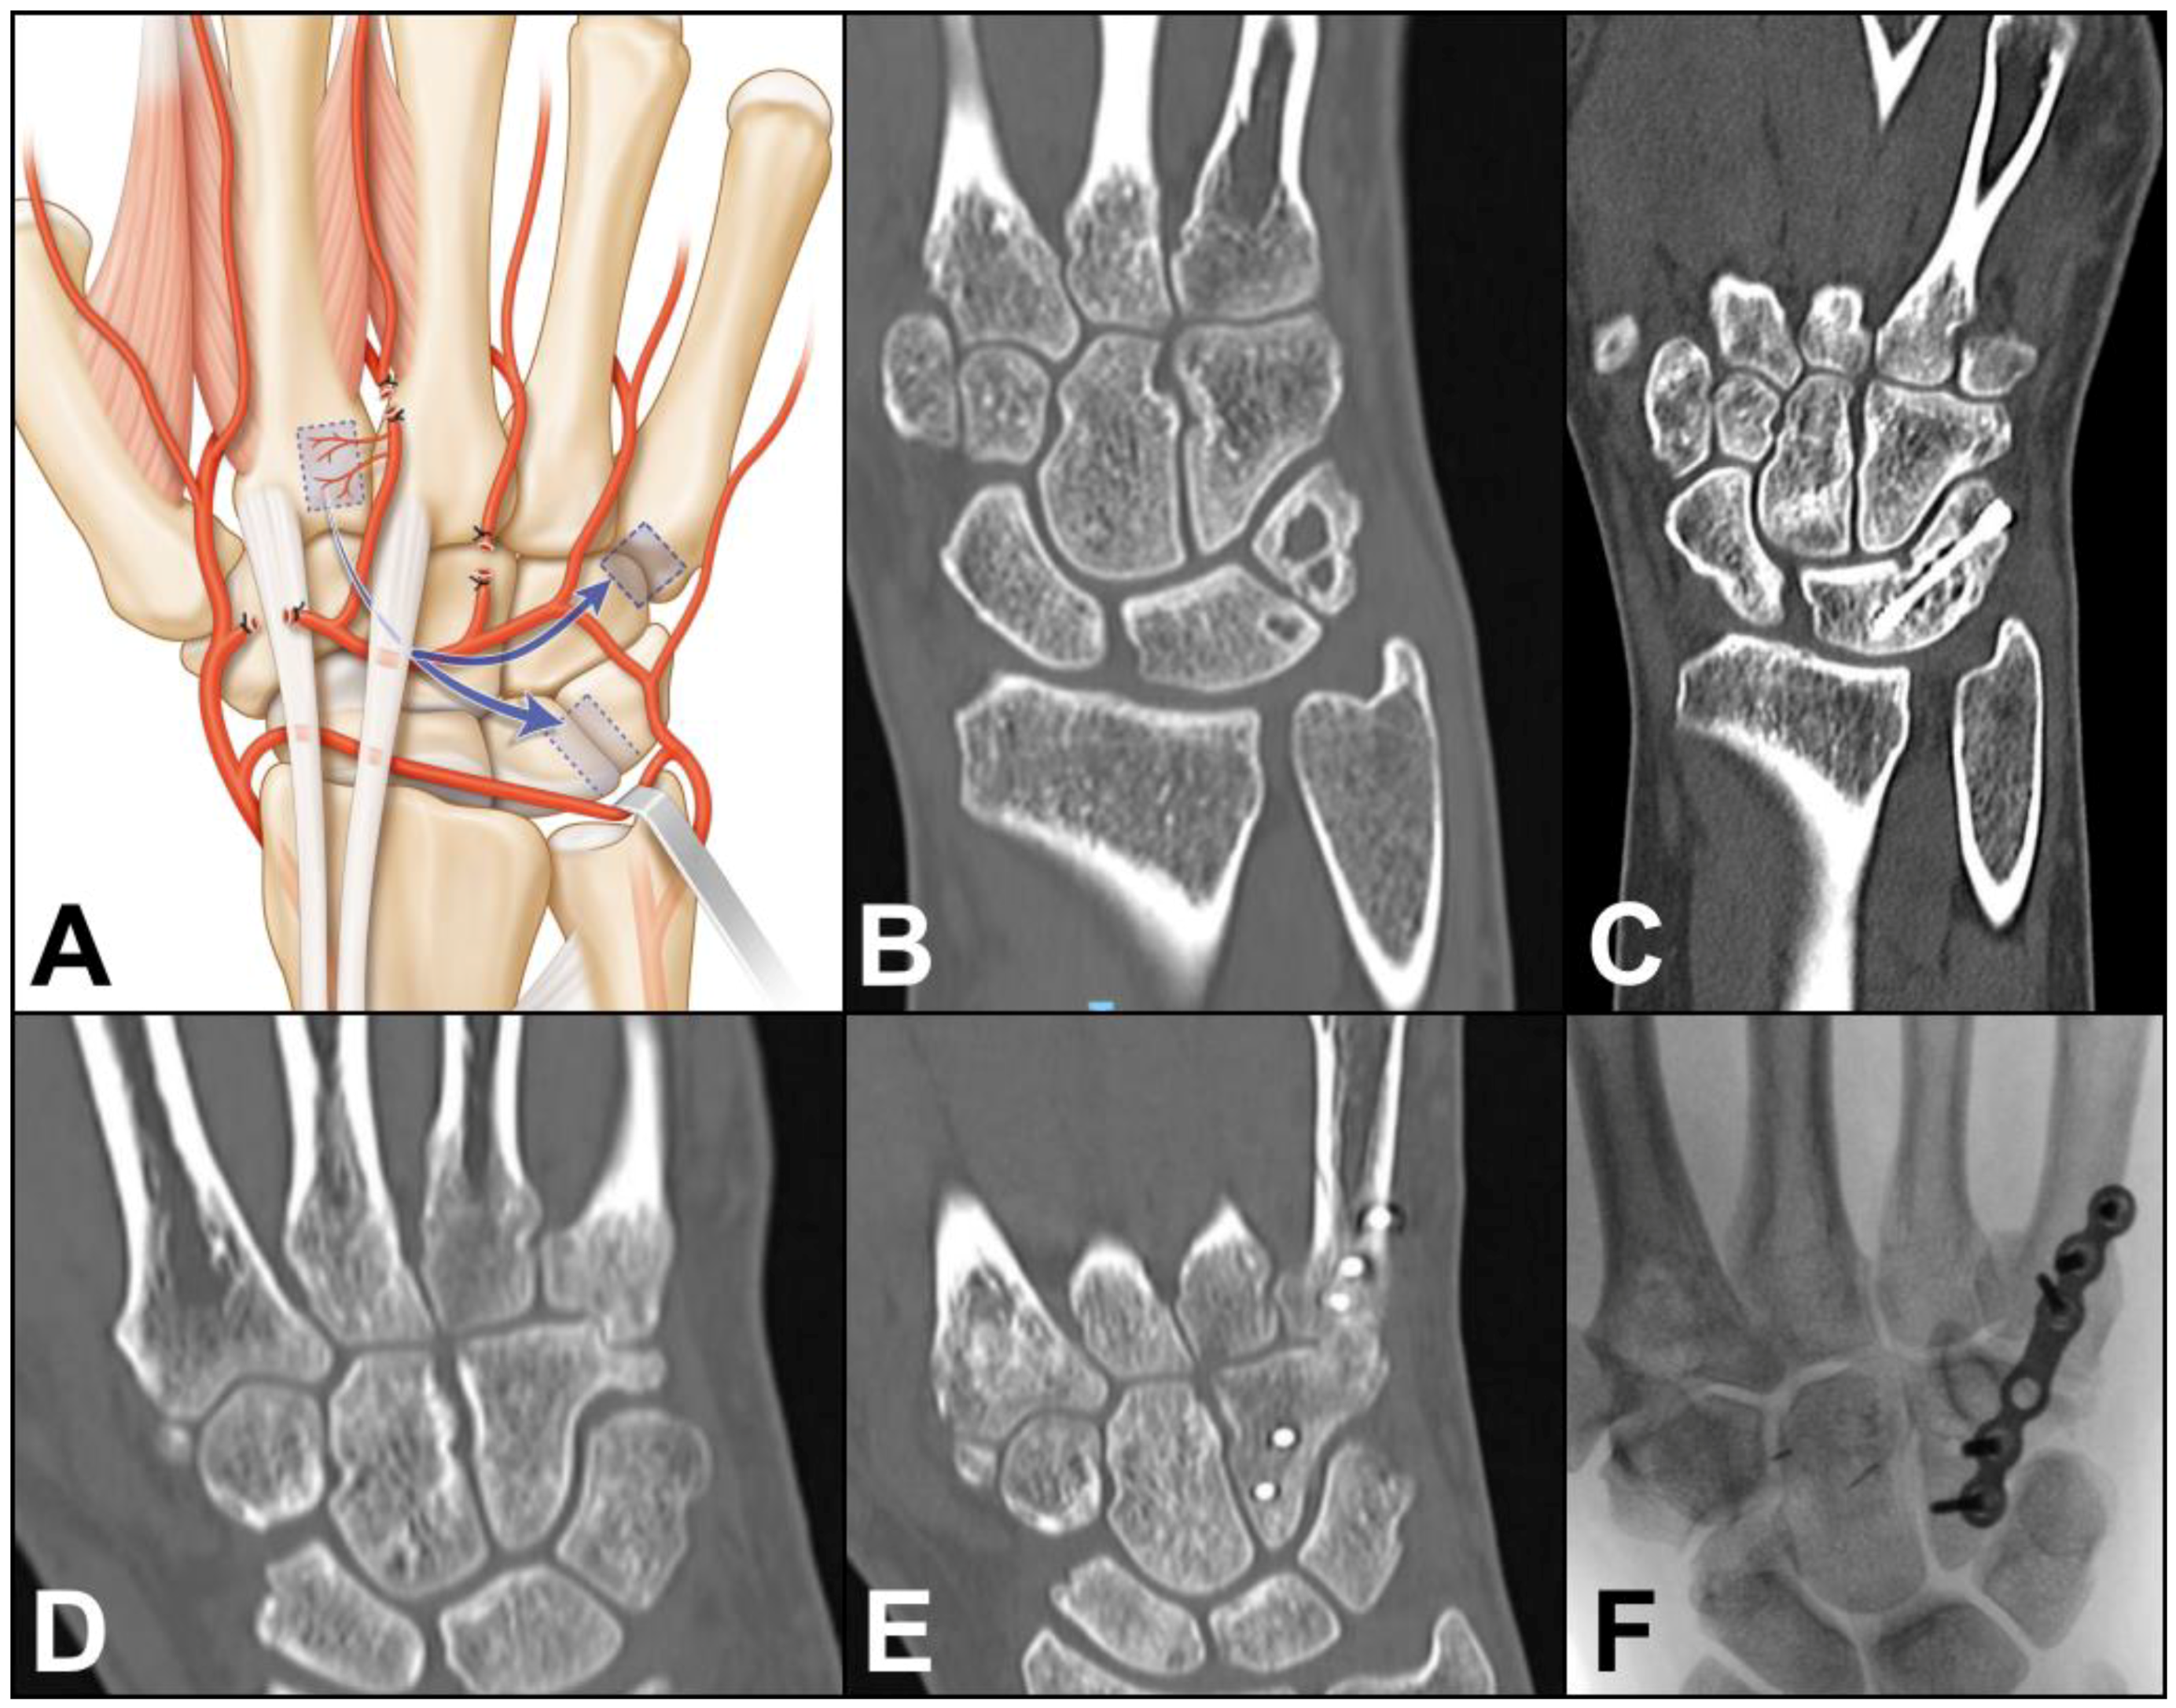

Case 2: A 30-year-old female developed painful arthritis of the right lunotriquetral joint. Surgery was proposed after failure of conservative treatment. An oblique incision was made from the base of the 2nd metacarpal to the lunotriquetral joint. Anastomosis between the dorsal carpal arch and the 2DMA was verified. The 2DMA was ligated distally to the base of the second metacarpal. The dorsal carpal arch was cut radially to the 2DMA origin and released up to the origin of the fourth dorsal metacarpal artery (Figure 4A). The arterial dissection is performed under the extensor tendons of the second to fourth rays. The size of the pedicled bone was 0.9 × 0.9 cm. The 2DMA flap was based on the ulnar side of the dorsal intercarpal arch. Fusion of the affected joint was achieved with a 3.0 mm CCS screw (Aptus, Medartis, Switzerland). A CT-scan confirmed bone union after twelve weeks (Figure 4B,C). No complication was observed at the donor site, and the CCS screw was removed after one year. Clinical and radiological outcomes were unchanged 2 years after surgery.

Figure 4. (A) Arterial anatomy, ligation of several arterial branches is necessary to allow the graft to reach the ulnar side of the carpus; Case 2. (B) preoperative CT-scan showing lunotriquetral arthritis; (C) postoperative CT-scan confirming fusion of the joint. Case 3. (D) preoperative CT-scan showing fifth carpometacarpal arthritis; (E,F) postoperative CT-scan and X-ray confirming fusion of the joint.

Case 3: A 39-year-old male developed painful arthritis of the fifth carpometacarpal joint (Figure 4D). Surgery was proposed after failure of conservative treatment. A transverse incision was made from the base of the 2nd metacarpal to the base of the 5th metacarpal. Anastomosis between the dorsal carpal arch and the 2DMA was verified. The 2DMA was ligated distally to the base of the second metacarpal. The dorsal carpal arch was cut radially to the 2DMA origin and released up to the origin of the fourth dorsal metacarpal artery (Figure 3A). The size of the pedicled bone was 0.8 × 0.8 cm. Fusion of the affected joint was achieved with a plate and 2.0 mm screws (Aptus, Medartis, Switzerland). Union was obtained after 10 weeks (Figure 4E,F). No complication was observed at the donor site, and the plate was removed after one year. Clinical and radiological outcomes were unchanged 1 year after surgery.